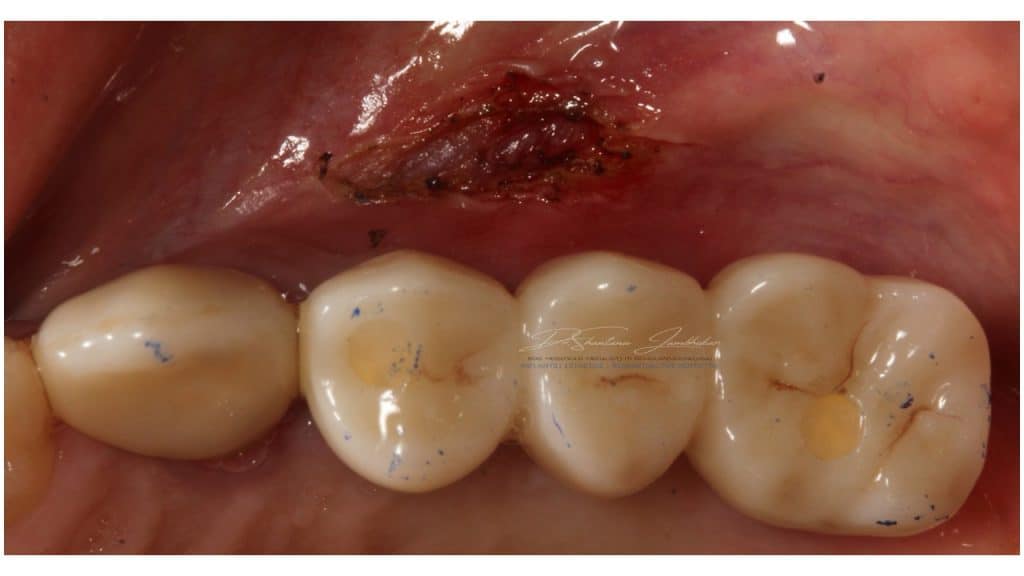

Biolase Epic X was utilized for minor frenectomy of the buccal frenii to eliminate the tension on the marginal ginvivae along the buccal aspect of the prosthesis.

Pontic Site modification with site 24 using Biolase Epic X laser

Laser frenectomy